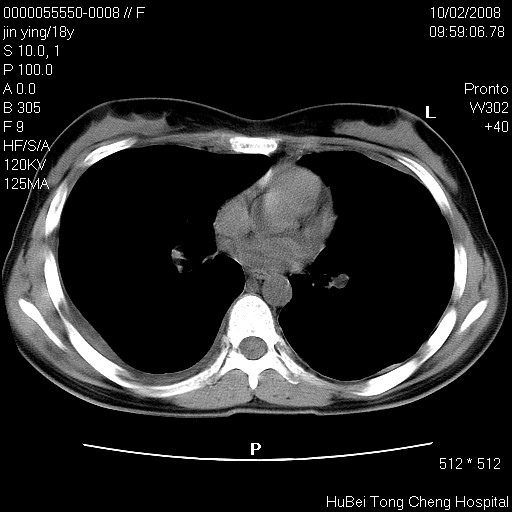

患者 女,18y。发热十余天,伴咳嗽。pe:t39⒈℃,bp 110/80mmhg,p 86次/min。神清,精神欠佳。双肺可闻及少许湿罗音。既往史不详。

临床诊断:肺部感染?

胸部ct轴位平扫(层厚10mm,螺距1.5,重建间隔10mm),图像如下: